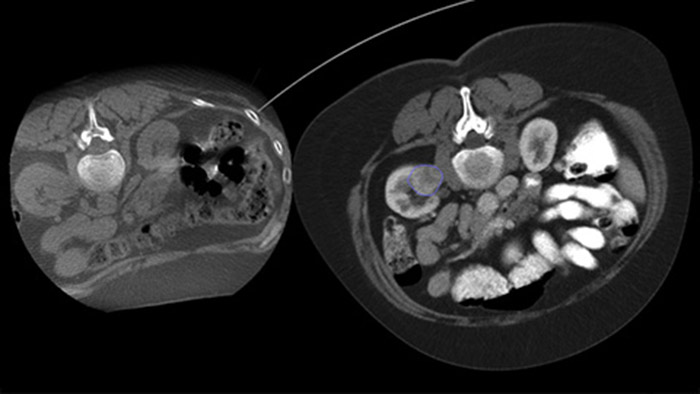

Mit Dual View kann ein 3D-Vorabbild (CT/MR/PET-CT) über ein intraprozedurales 3D-CBCT-Dual-Bild gelegt werden, um die Läsionen besser sichtbar zu machen und entscheidende Informationen für die Nadelplanung zu erhalten.

Mithilfe eines nach der Ablation erfassten CBCT-Bilds können Sie die Tumorabdeckung und damit die Vollständigkeit der Behandlung verifizieren.